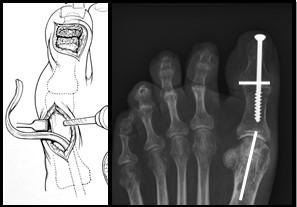

Longus naar brevis transfer

Aan de buitenzijde van de enkel lopen 2 spieren: de peroneus longus en de peroneus brevis. De longus gaat onder de voet door naar de grote teen. De brevis gaat naar de basis van de kleine teen. Vaak is de longus nog sterk en de brevis niet meer. Door de longus door te snijden en vast te maken aan de brevis zorg je voor meer kracht aan de buitenzijde van de enkel/voet en tevens voor een afname van de krachten die de grote teen omlaag trekken (de laatstgenoemde krachten zorgen voor een toename van de holling onder de voet)

Figuur 2: De peroneusspieren. Het litteken komt in de richting van de beide spieren (zwarte streep). De longus snijden we door en hechten we vast aan de brevis.